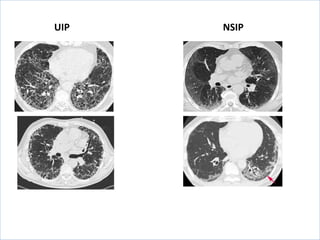

UIP vs NSIP

UIP NSIP

Histology can be UIP or NSIP

Usually UIP Usually NSIP

Imaging: thickened interlobular septa, ground glass

infiltration, and honeycombing in a sub-pleural and

basal distribution